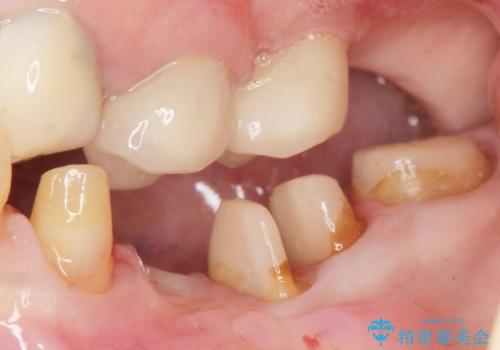

虫歯を丁寧に除去した後に歯根を分割し、骨を削合して健全歯質を露出させる骨外科手術を行いました。

手術後に根管治療を行い、歯肉と骨の治癒を十分に待った後ブリッジによる補綴治療を行いました。